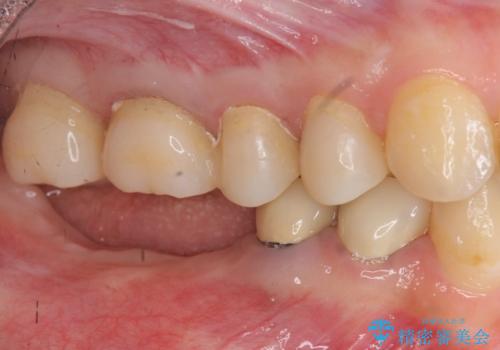

虫歯や咬合関係・歯槽骨の吸収・根尖病変・歯の欠損・複合的な問題を一つずつ解決し、

安定した噛み合わせの構築・歯ブラシのしやすい環境の整備・歯内歯周の感染除去・造骨を伴うインプラント治療

を行い、長期的な予後を見込める口腔内環境を確立、整備して行きます。